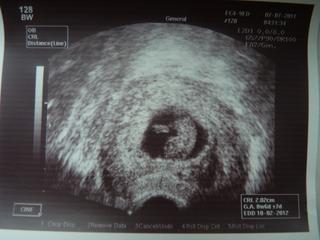

@xxx.klarka jeej krasna fotecka . . . blahozelam 😉

...tak u nas srdiecko potvrdene a aj tehu knizka uz je doma... 🙂 ...podla poslednej mrchy je sice termin 15.2., podla utz az 27., kedze ani srnka netusi, kedy som mala ovulku pri mojom 40 dnovom cykle... 😅 ...ale ked pojde skor , tak ako mala, tak to bude aj tak jedno... 😀 😀 😎